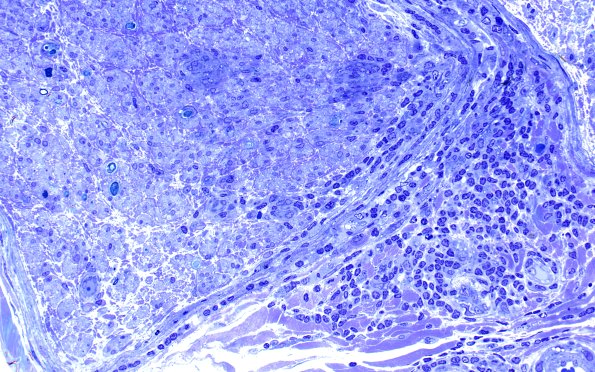

2D4 sarcoid & Chronic Denervation (Case 2) Plastic 40X 2

Higher magnification of the granuloma. (Plastic sections)